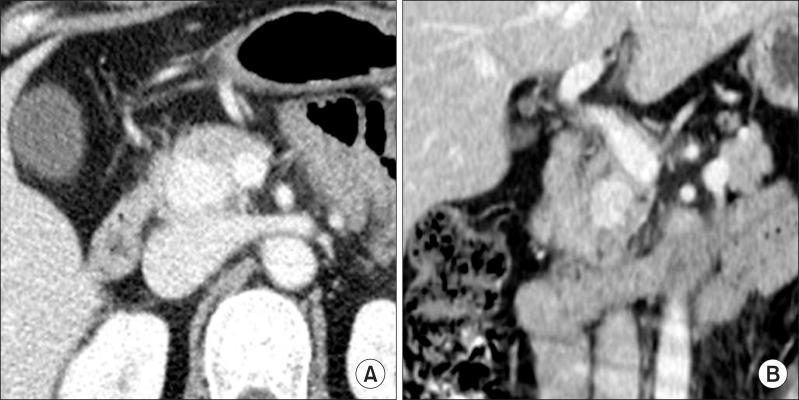

Solid hamartoma of the pancreas is very rare, and only 3 cases have been reported thus far. A patient underwent pancreaticoduodenectomy due to a mass in the head of the pancreas which was suspected to be a borderline malignant tumor, but the histologic diagnosis turned out to be myoepithelial hamartoma (MEH) or adenomyoma. It was characterized by benign duct and glandular structures surrounded by proliferating smooth muscle, and acinus formation was not observed. Immunohistochemical stain for smooth muscle actin (SMA) was positive in spindle cells, and CD34 was negative, differentiating it from the three previously reported cases of solid hamartoma of the pancreas. MEH is an entity that is on the same spectrum as heterotopic pancreas. MEH is rare and has usually been reported in the gastrointestinal tract. To the best of our knowledge, MEH has never been reported in the pancreas. Therefore we report the world's first documented case of MEH of the pancreas.